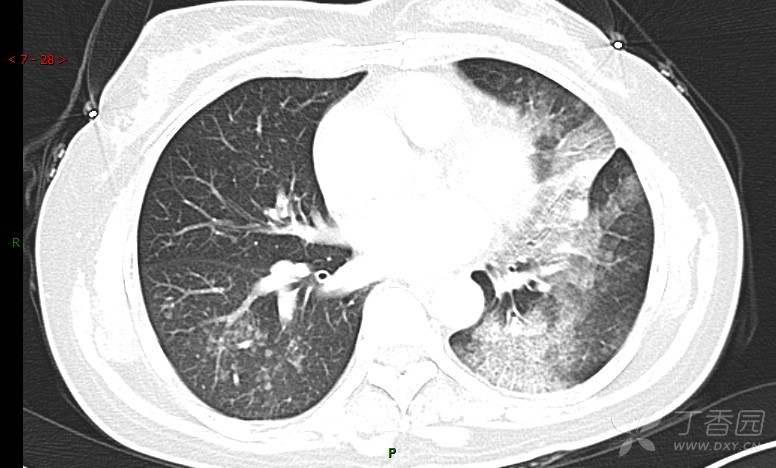

腺泡结节影,蜂窝征,这些都在提示……(病例3连发,附其他2例链接,病理已公布)

咳嗽1年余,加重7天。

患者于1年余前始受凉后出现咳嗽,多为干咳,未在意,未到医院就诊。近3月患者出现咳痰,多为黄色粘痰,量大,伴乏力,偶有头晕、心慌,无发热、胸痛、憋喘,无低热、盗汗、咯血、胸痛,无头痛,无恶心、呕吐、腹痛、腹泻,无尿频、尿急、尿痛,在当地诊所给予抗感染等对症支持治疗(具体药物及剂量不详),症状仍时有反复。患者于1月余前到外院就诊,行胸部CT提示双肺炎症,左肺重,考虑为“间质性肺炎”,给予“左氧氟沙星、利巴韦林、头孢哌酮舒巴坦钠注射液”治疗,复查胸部CT示病灶吸收不理想,后出院继续于诊所对症治疗(具体药物及剂量不详),效果欠佳。7天前患者无明显诱因出现上述症状加重,为求进一步诊治,特来我院就诊,我院门诊以“肺炎(重症)?”收入留观室,留观室给予“盐酸莫西沙星氯化钠”等对症治疗后,今日转入我科。患者自发病以来,神志清,精神差,饮食正常,睡眠增多,大小便正常,体重近3月减轻5公斤余。